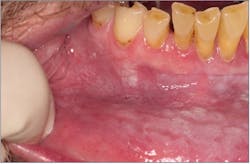

Frictional keratosis

Frictional keratosis (figure 1) is a white keratotic lesion on the oral mucosa that results from a chronic mechanical friction by various oral irritants or habits. These lesions appear on the keratinized or nonkeratinized tissues and present as diffuse plaques, pale translucent to dense white and irregular.2 As the name implies, frictional keratosis is diminished with removal of the causative factor. If cessation of the irritant does not result in clinical improvement, a biopsy should be performed.